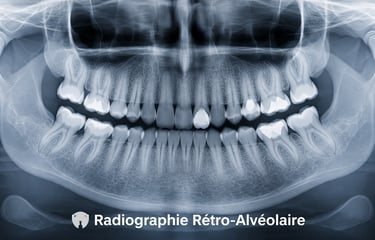

Radiographie Rétro-Alvéolaire

La radiographie rétro-alvéolaire est un examen précis permettant de visualiser la dent dans sa totalité, y compris la racine et l’os environnant.